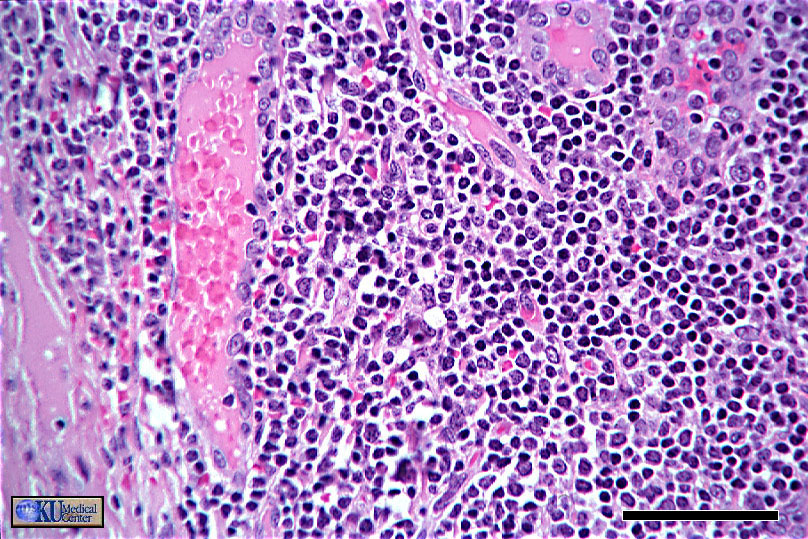

Slide 17 Post-Capillary Venule

The post-capillary venule is the main site of leukocyte extravasation. Here in a lymph node, it has a high (cuboidal) endothelium. Note the longitudinal cut on the left and the two cross sections on the right.

Bar = 50 Microns